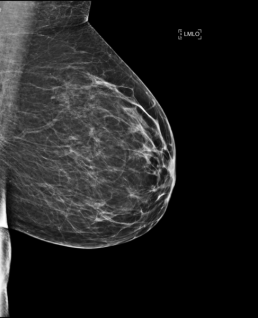

Case of the week (week 13, 2023)

BILATERAL SCREENING 3-D MAMMOGRAM

There are scattered areas of fibro-glandular density. There is a 6 mm nodular asymmetry with irregular margins in the deep outer right breast seen in the cc projection. There are a few associated small calcifications.

MammoScreen®: A collocated mass with micro calcifications is detected in both the RIGHT CC and RIGHT MLO. The system gave it a MammoScreen ScoreTM of 6. No detections observed in the left breast, it is scored a 1.

MAMMOGRAM FINDINGS: Subtle focus of asymmetric distortion appearing to contain a few indeterminate calcifications are confirmed at approximate 12:00 in the right breast half way back.